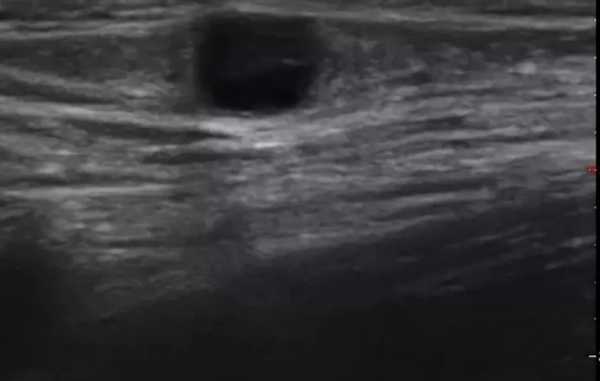

Мы выявили совершенно другую УЗ-картину состояния пальпируемых лимфатических узлов при динамической оценке у больных с синдромом иммунодефицита. Оцениваемые лимфатические узлы имели эхографические признаки доброкачественного процесса, в большинстве наблюдений их размеры превышали 2-2,5 см. При этом во всех случаях дифференцировались составные части лимфатического узла. Определялся узкий кортикальный слой и широкая гиперэхогенная сердцевина при сохранении овальной конфигурации и соотношении поперечного/переднезаднего более 1.

При повторных УЗ осмотрах на фоне массированной противовоспатительной терапии было отмечено увеличение числа лимфатических узлов вовлеченных в процесс активизации. При этом заметной перестройки эхоструктуры и уменьшения размеров в наблюдаемых лимфатических узлах отмечено не было (рис 4).

Рис. 4. Варианты изображения увеличенного лимфатического узла с УЗ-признаками доброкачественной аденопатии у больного с синдромом иммунодефицита.

- у больных с воспалительными процессами на фоне синдрома иммунодефицита не было отмечено УЗ признаков активизации коры, что в контрольной группе проявлялось увеличением толщины области ворот и тенденцией к округлой конфигурации. При динамическом наблюдении УЗ-картина свидетельствовала о вовлечении в процесс все новых лимфатических узлов. "Старые" же лимфатические узлы на фоне проводимой терапии не имели УЗ признаков положительной динамики.